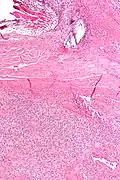

Solitary fibrous tumor - low magnification. H&E stain.

Solitary fibrous tumor - low magnification. H&E stain. -